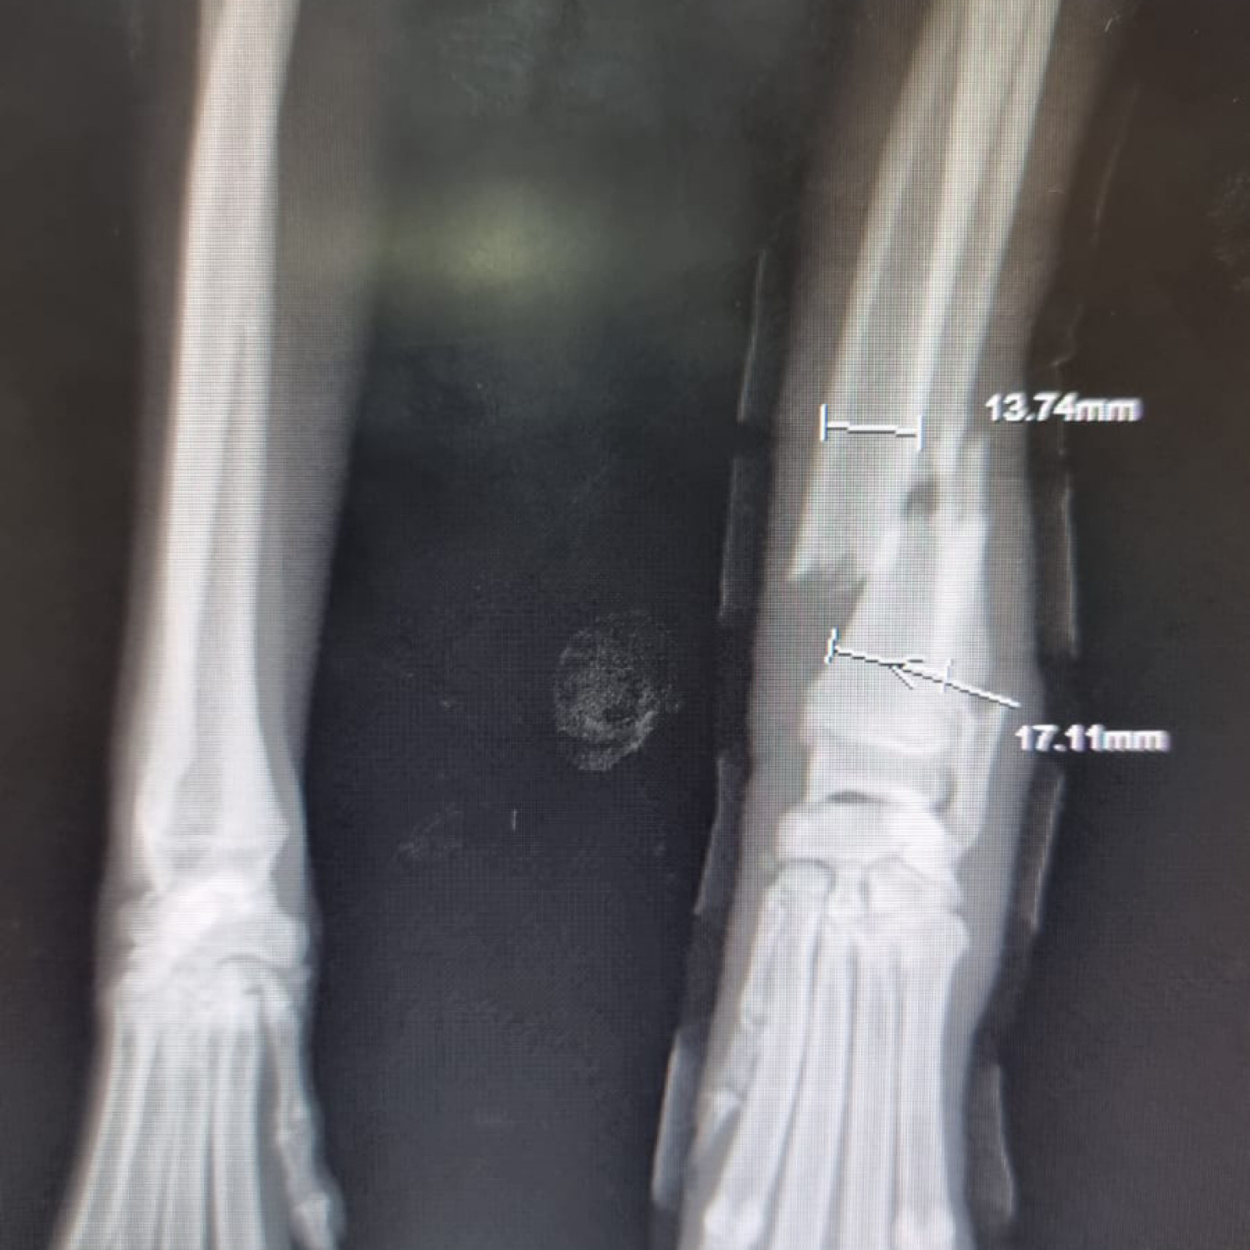

Hope konnte geröntgt werden. Was man nun sieht, tut einem schon vom hinsehen weh...

Das Gute: mit den Bildern wissen wir nun, was genau los ist und dementsprechend, was zu tun ist.

Derzeit wird ein Transport organisiert. Dann gehts für Hope voraussichtlich am Sonntag ab nach Phuket, wo man sie dann hoffentlich operieren kann.